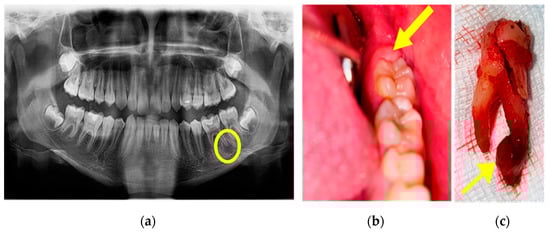

A Pediatric Neuropsychiatry Consult was also performed after which the diagnosis of acute flaccid paralysis and anxiety disorder was established. When the general state of health was stable, an OPG was performed, and on the tooth 3.6, a deep cavity damaging the pulp chamber was observed, and a periapical reaction was evident at the distal root (Figure 8a). Intraorally, we observed that the operculum of tooth 3.7 was partly present on the distal occlusal surface (Figure 8b). It was decided to extract tooth 3.6 and curettage the periapical lesion (Figure 8c).

Figure 8. (a) OPG showing periapical lesion on distal root of tooth 3.6, (b) the mucous cap on 3.7 (coronal distal part), and (c) extraction of tooth 3.6 and the periapical lesion.